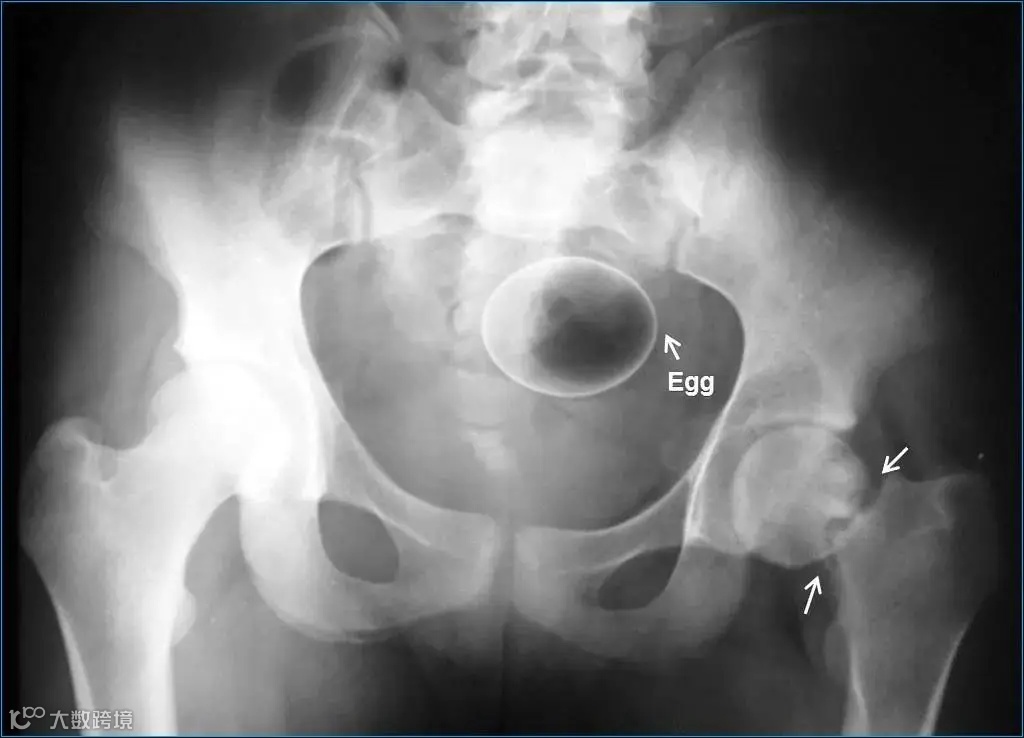

鸡蛋▽

这些本不该出现在肛门内的东西,总有人会“一不小心”塞进去了,这对菊花来说是很大的一种伤害。